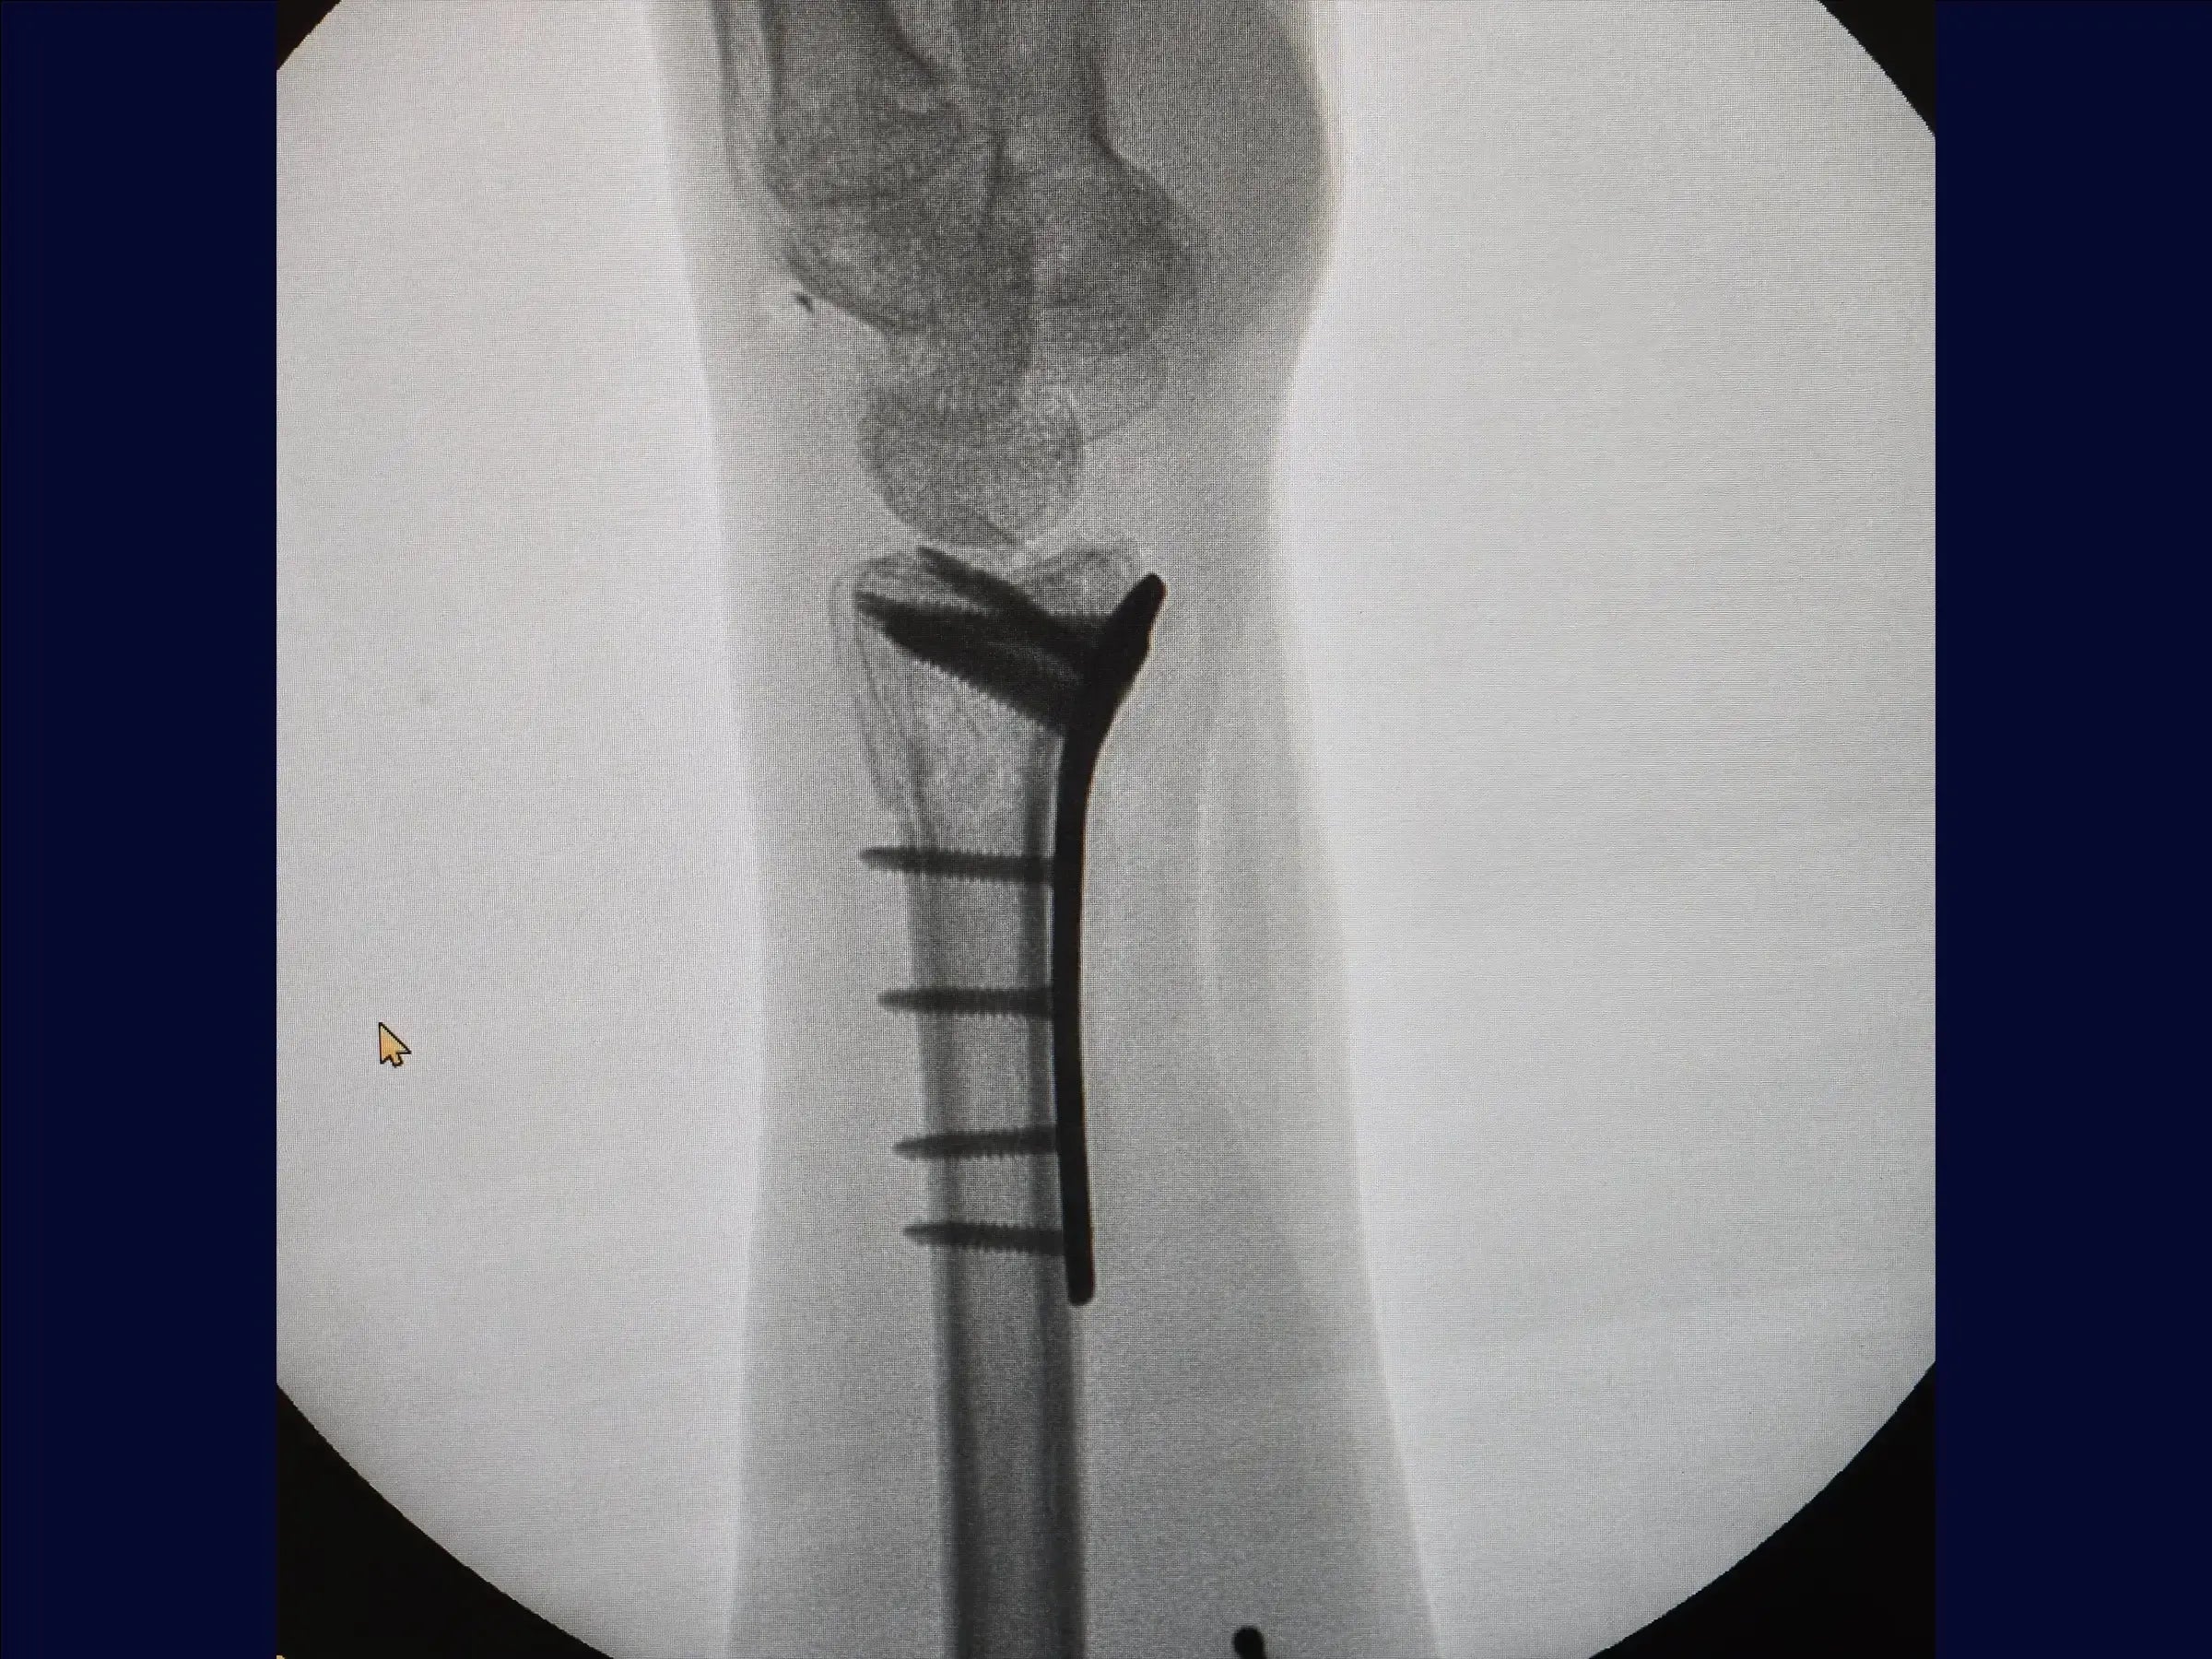

Fractura multifragmentaria del radio distal (abordaje volar)

Domine el tratamiento quirúrgico de las fracturas multifragmentarias del tercio distal del radio con esta formación centrada en el abordaje volar. El procedimiento busca restaurar la longitud radial y la congruencia articular mediante una combinación de tracción manual, fijación percutánea provisional y una estrategia de fijación con placa volar y tornillos de diferentes longitudes para estabilizar los múltiples fragmentos, incluido el componente dorsal, sin necesidad de un abordaje dorsal adicional.

- Preparación y fijación volar: Se reemplaza el retractor, se limpian los vértices de la fractura y se inserta la placa, respetando el límite articular. Se comienza con un tornillo cortical en el orificio oval para compresión. Se utilizan tornillos cortos para fijar el fragmento volar y, con maniobras digitales, tornillos largos estabilizan la superficie dorsal sin necesidad de otro acceso. Los tornillos cortos se reemplazan por tornillos largos (18-20 mm), incluyendo la estiloides, completando la osteosíntesis en los orificios restantes.

- Cierre y resultados finales: Se sutura el pronador cuadrado en línea recta. La reducción es satisfactoria, con una anatomía del radio prácticamente normal. Se realiza un cierre cutáneo para obtener un resultado satisfactorio.